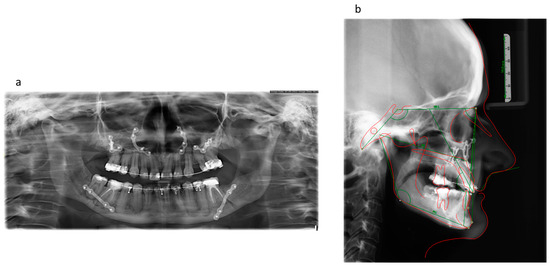

2. Case Report